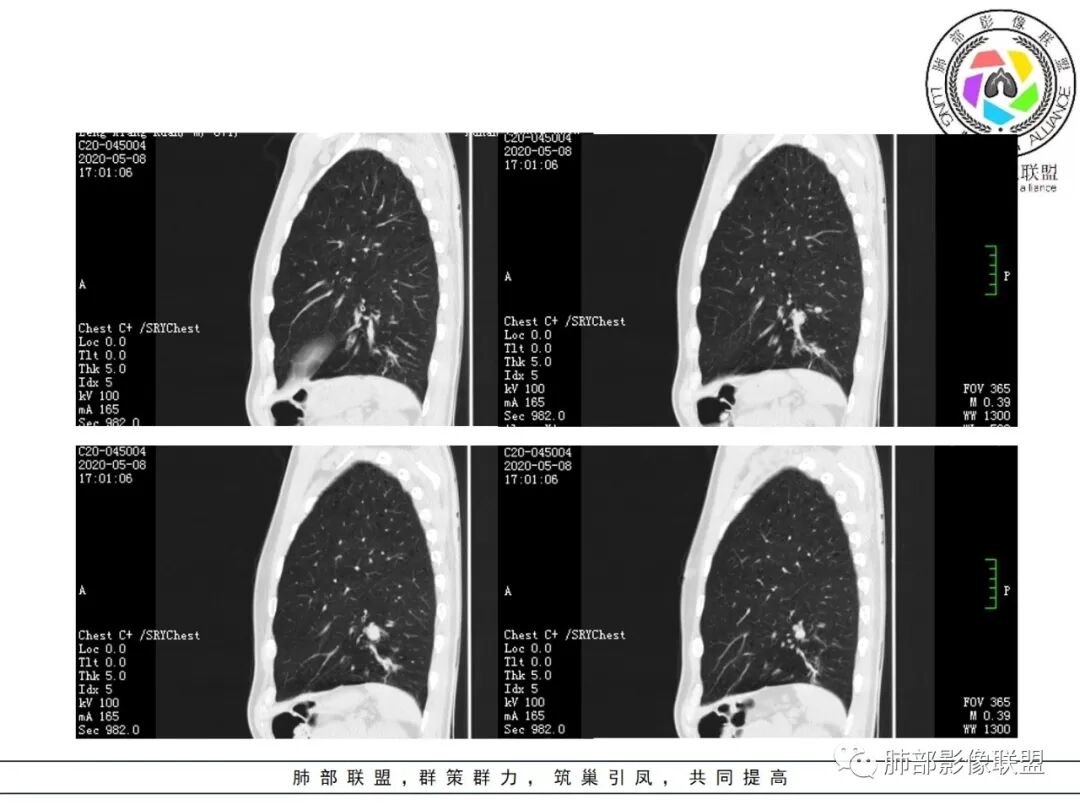

大雄:抗感染不吸收还是要警惕癌尤其主动脉旁的病灶红星:老年患者,咳嗽咳痰两个月,既往有糖尿病病史10年,左肺下叶后基底段斑片状、条索状、斑点状多形态的病灶,病灶内可见支气管征以及狭窄扩张的支气管影像。重建图像上可见到病灶沿支气管爬行。增强扫描病灶轻度强化,临近胸膜增厚。首先考虑感染性的病变,结核性的可能性最大。鉴别诊断上注意排除肺克以及淋巴瘤。三个石头:左肺下叶多发斑片,结节,条索,多态性?结核?多个结节边缘长毛刺,胸膜牵拉,分叶。矢状位支气管走行扭曲,没有完全阻塞,应该有粘液栓,有点像指状。主动脉旁病灶边缘平直,部分有鹏隆感,延迟强化。抗炎病灶变化不明显,结核?真菌?肿瘤也除外不了。没意见:左肺下叶基底段结节,膨隆、深分叶,毛刺,内侧串珠结节,中轴间质增厚,管腔狭窄,后基底段亚支不张,强化情况不明,考虑恶性,腺癌可能性大,另指套样征像,支气管壁增厚,不除外霉菌感染流心明智:老年患者,咳嗽咳痰2月。既往糖尿病史10年。胸CT:左肺下叶基底段多发结节影、斑片影、条索影,多数结节影沿支气管血管束分布,支气管壁厚,部分结节分叶、指状突,后基底段支气管狭窄闭塞。重建可见到病灶沿支气管爬行。增强扫描病灶明显强化,部分斑片影内可见低密度灶。普通抗感染无效。考虑:恶性病变,鳞?小?鉴别TB、隐球等。王秀仙:左肺下叶沿支气管血管束分布斑片、结节影,部分呈管状铸型生长,管腔狭窄,后基底段支气管阻塞,降主动脉旁不张实变,增强扫描病灶轻度强化,抗感染2周无吸收,考虑鳞癌。鉴别结核。蓝天白云:肺野内老年男性,咳嗽咳痰,有糖尿病病史,抗炎治疗无吸收。影像表现为左肺下叶支气管腔内结节影,支气管壁增厚,远侧小花小草,增强后实变影均匀强化,考虑鳞癌伴远端阻塞性炎症,鉴别结核。采莲:老年男性,咳嗽咳痰2月,有糖尿病史,左肺下叶沿支气管分布多发结节条状影,结节影不规则有分叶,成串珠样,靠下结节影成条索影,周围有空气储留,靠近主动脉不规则块状影,边缘平直,周围支气管壁增厚,支气管进入后阻塞,有糖尿病史,首选考虑炎性肺结核可能性大,鉴别肺鳞癌。了:左肺多发结节影,实性结节,,磨玻璃结节,左肺门结节影,深分叶,彭隆感,有血管滋养,考虑肿瘤,抗感染后病灶无吸收,感染不像,结节有强化,无卫星灶,结核可以排除不再涩的柠檬:老年男性,吸烟史,糖尿病史,咳嗽咳痰2月,抗感染2周无效。左下基底干及各分支管壁较弥漫增厚,伴支气管粘液栓,远端阻塞性肺炎,后基底段部分不张实变。先考虑感染病变,常规抗炎无效,需考虑结核、曲霉等,不能排除鳞癌合并感染,建议支气管镜检查。

影像所见:

支气管壁厚,支气管腔内高密度影填充。

周围散在斑片影及结节影,类似“小花花草草”的感觉。

2.关于支气管:上述病灶辖区外侧段支气管截断,环壁结节,远端阻塞性肺炎,是肺癌的重要征象。